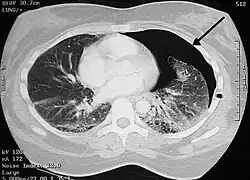

![]() CT snímek levostranného pneumotoraxu | |